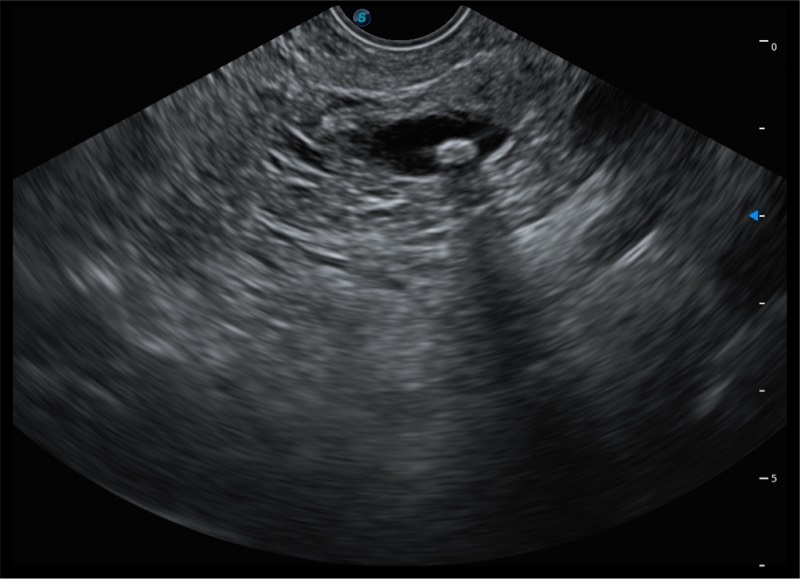

• 搭载百万级CMOS成像技术

• 及自主研发凸阵换能器,

• 可呈现优质的内镜和超声画面

基于二十年的超声技术积累,哈哈体育官网提供了最新一代的独立超声主机,在提供高质量图像的同时满足多学科使用。具备常见多普勒技术并提供弹性成像、声学造影等高端影像技术。新一代传感器具有更强的抗干扰能力并减少图像伪影。

• 4-12MHZ宽频输出